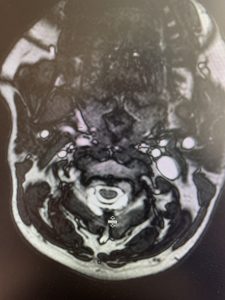

This 57 year-old male presents with severe neck, left shoulder and arm pain and weakness in his hand since being involved in a motor vehicle accident nine months prior. The patient had subsequent left shoulder surgery although he still complained of pain postoperatively and his weakness persisted. He was on no blood thinners. He underwent imaging. The cervical spine MRI revealed an extensive dorsal epidural collection from C1-2 through C5 with associated spinal cord compression. In addition there were multisegmental degenerative changes with foraminal stenosis worse at C4-5 (Fig. 1a and 1b).

(1a) Sagittal and axial T2-weighted cervical MRI demonstrating extensive dorsal epidural collection with hyperintense signal consistent with fluid causing spinal cord compression.

It was felt that the patient was unstable and the patient had signs of early cervical myelopathy secondary to spinal cord compression. The patient consented to undergo exploration and evacuation of the collection and to decompress and stabilize the cervical spine. Upon laminectomy we noticed a ruptured C3-4 interspinous ligament that was consistent with the preoperative imaging studies. After revealing the epidural space during the laminectomy, a large dorsal membrane or pseudomeningocele was noted above a clear fluid collection that was posterior to the dura that was compressing the spinal cord. This membrane was fenestrated and we evacuated the collection which was consistent with CSF. Also during the course of the laminectomy we noted that the source of the CSF leak to be on the left at the takeoff of the C4 nerve root for which the dural sleeve was “degloved” but the fascicles were intact. We repaired with muscle and dural sealants. We completed a C2-C7 laminectomy. The patient had an additional fusion C3-C6 with segmental instrumentation to prevent kyphotic deformity.